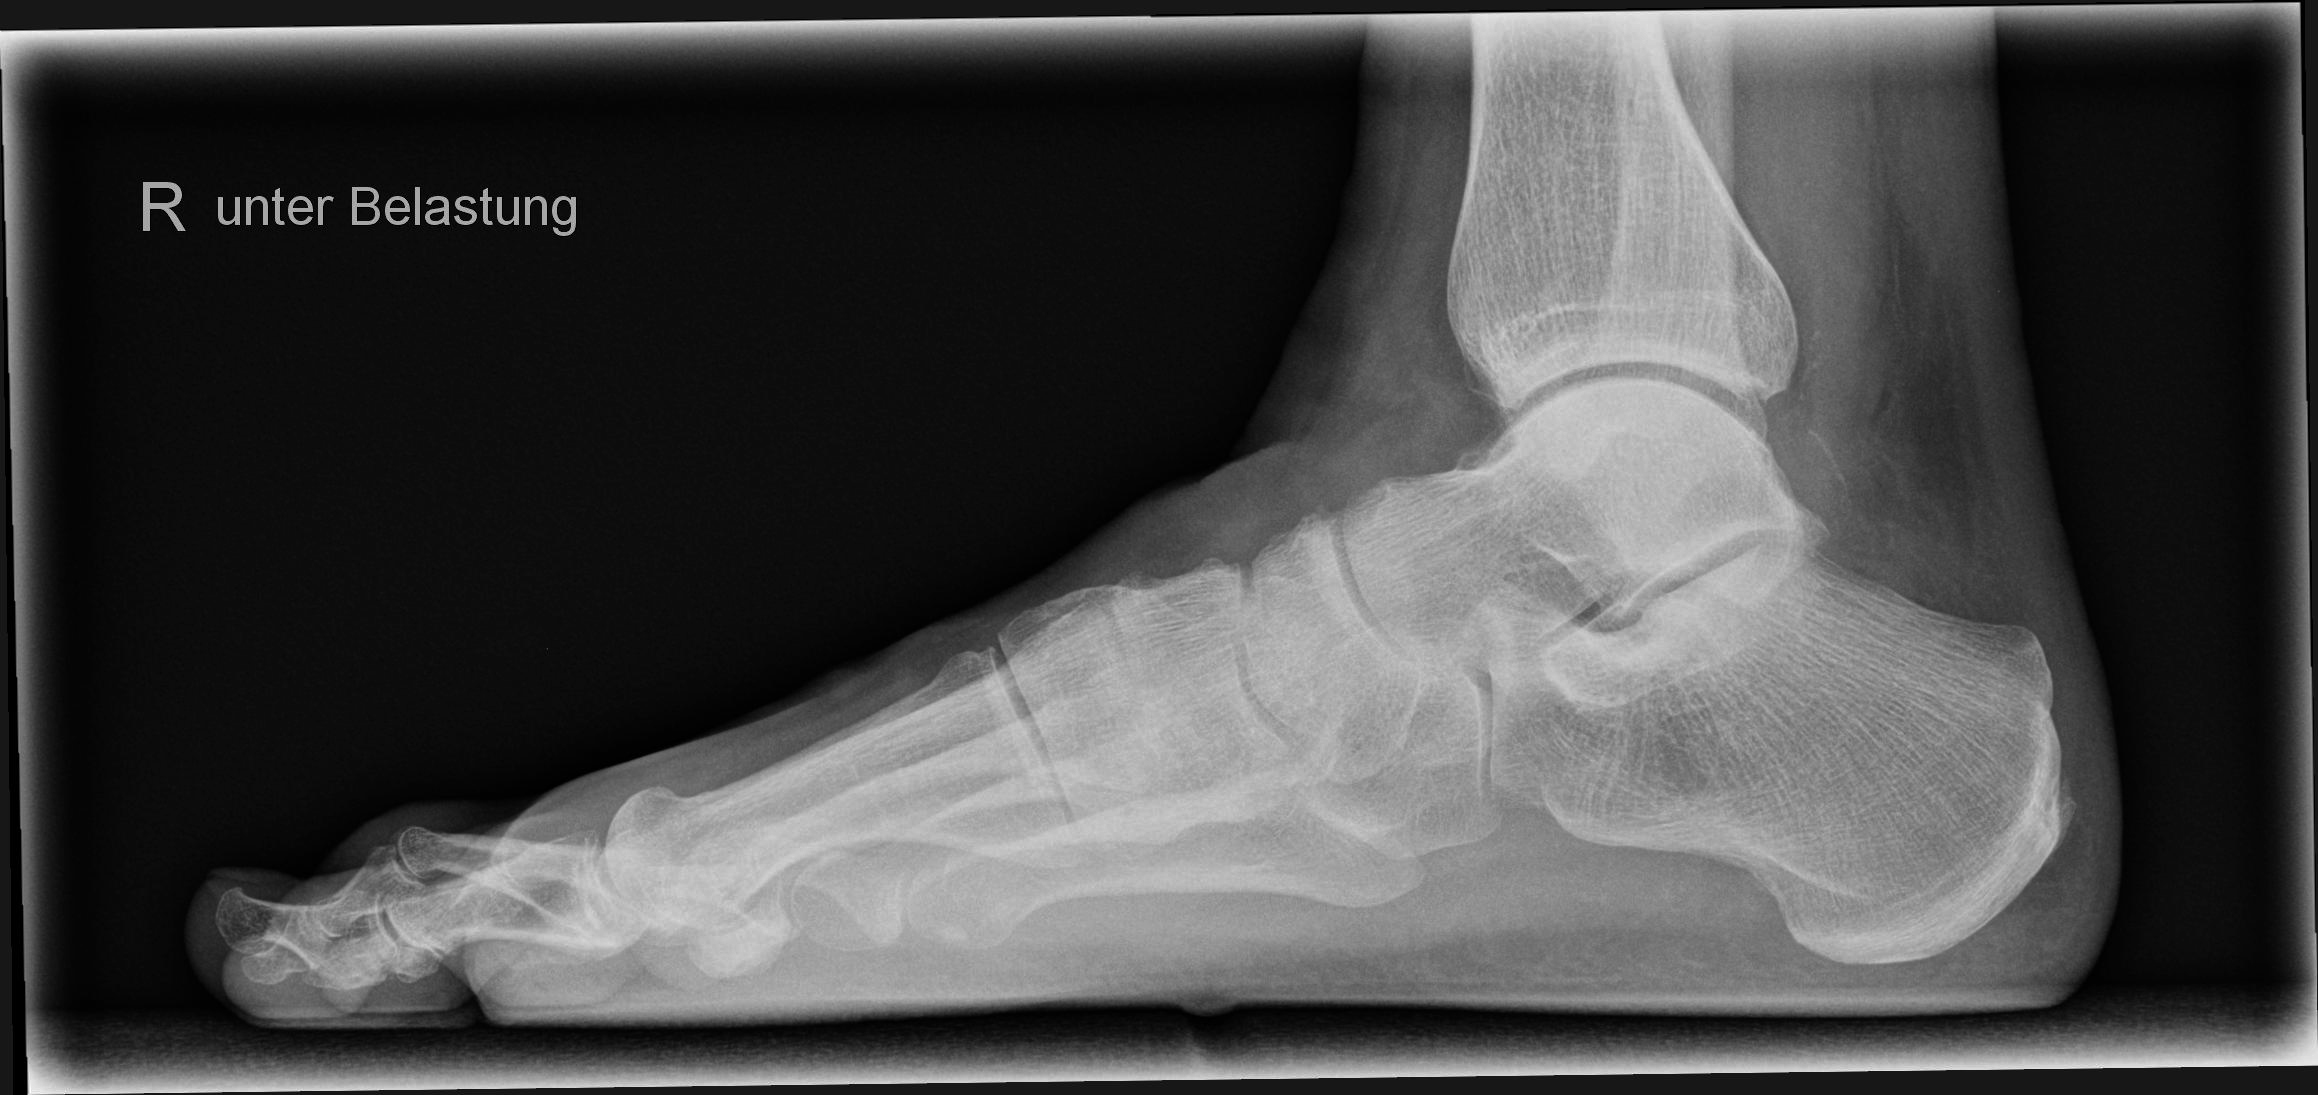

Fuß seitlich unter Belastung

Zur Begutachtung eines Senk- und Plattfußes oder aber zur Beurteilung der Fußachse und des Halux.

Lagerung

stehend mit Außenseite zum Bildempfänger auf einem Sockel

zweiten Fuß nach hinten versetzen um das Gleichgewicht zu halten

untersuchenden Fuß voll belasten

zum Halt sollte sich der Patient auch irgendwo am Stativ festhalten

Qualitätskriterien

Seitliche Aufnahme des ganzen Fußes. Die Mittelfußknochen und Phalangen überlagern sich. Oberes und unteres Sprunggelenk sind gut einsehbar. Überlagerungsfreie Darstellung des Fersenbeins.